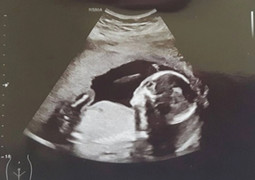

Nữ bác sĩ giữ lại nhịp tim mong manh của thai nhi

Đối mặt ca song thai chung bánh nhau nguy kịch, TS.BS Phan Thị Huyền Thương cùng ê-kíp can thiệp bào thai, giành lại sự sống cho em bé từ trong bụng mẹ.